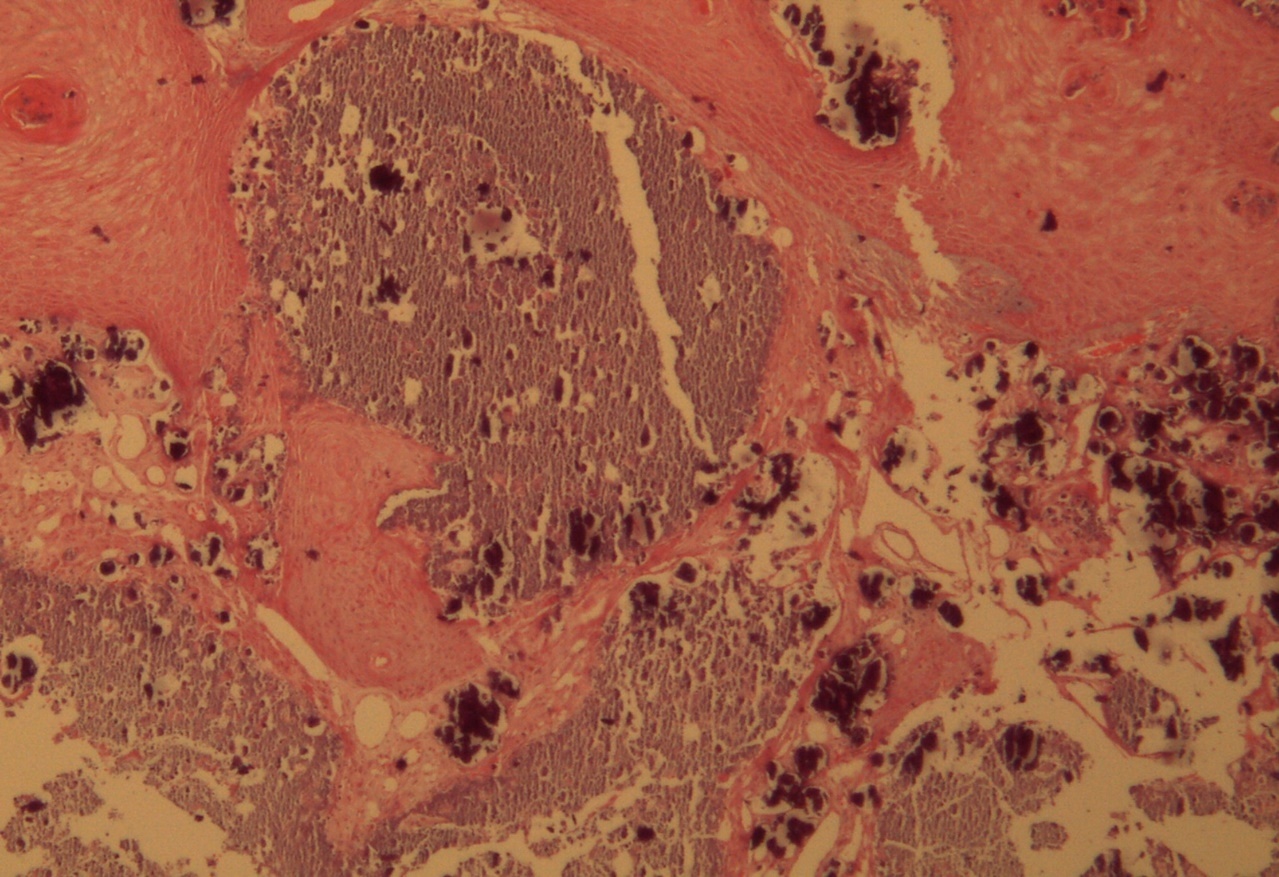

A 9-year-old male patient who was treated in the dermatology service for a progressively growing keratotic nummular dermal lesion on the right knee. With the clinical judgment of viral wart, the lesion was removed. In the Pathology Service, a nummular keratotic lesion of 0.5 cm in maximum dimensions was received, which crackled when cut. Figure 1, Figure 2, Figure 3, Figure 4, Figure 5

Figure 1.Hyperkeratosis, hypergranulosis, proliferation of dermal vessels, and surface and deep calcium deposits. HE. 100x.

Figure 2.Common wart with calcium foci at the level of the dermal vessels grouped in lobules. HE. 200x.

Calcinosis cutis refers to the deposit of calcium salts on the skin. It generally constitutes a morphological type of dystrophic calcium deposit, related to different types of lesions or injured tissues (in this case a common wart) without alterations in calcium metabolism in biochemical studies, typical of metastatic calcifications.